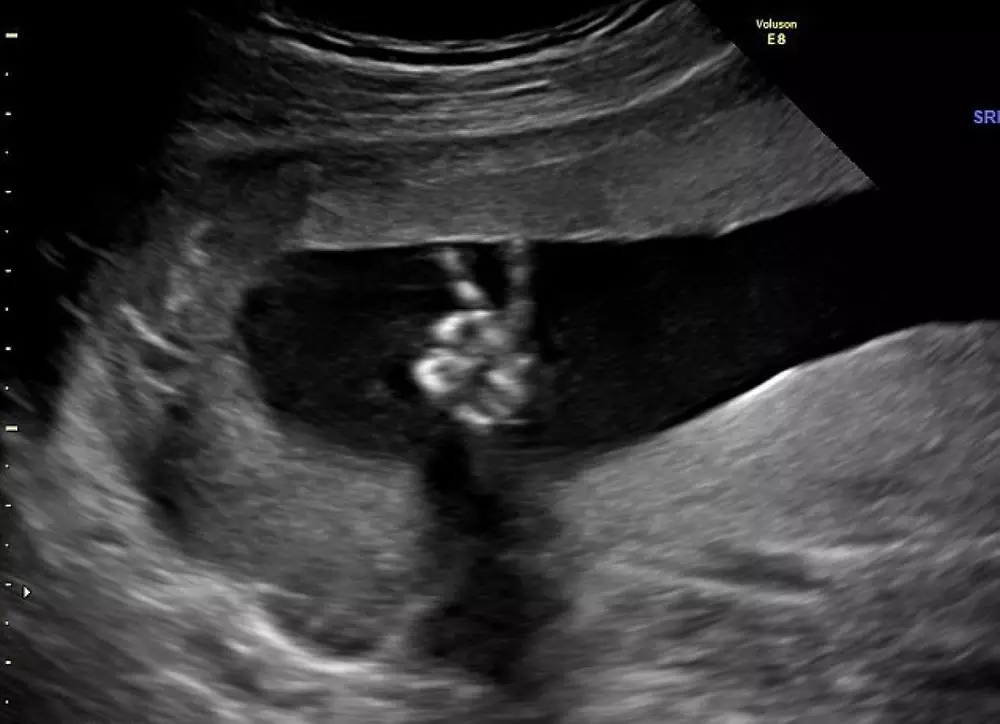

Когда беременная англичанка Ди Парсонс отправилась вместе с мужем Эдом на плановое УЗИ, то не ожидала увидеть на снимке ничего принципиально нового. Однако взглянув на готовую фотографию, 35-летняя женщина обомлела - ее 20- недельный малыш показывал родителям дерзкий жест "победы", пишет британская газета Daily Mail.

Сотрудница больницы, проводившая ультразвуковое обследование, также немало удивилась. По ее словам, она никогда не видела ничего подобного.

Супружеская пара, которая проживает в графстве Суррей, посчитала жест ребенка счастливым знаком. Эд и Ди решили, что если у них родится мальчик, то его непременно назовут Уинстон в честь Уинстона Черчилля, который во время Второй Мировой войны усиленно популяризировал этот символ для обозначения победы.